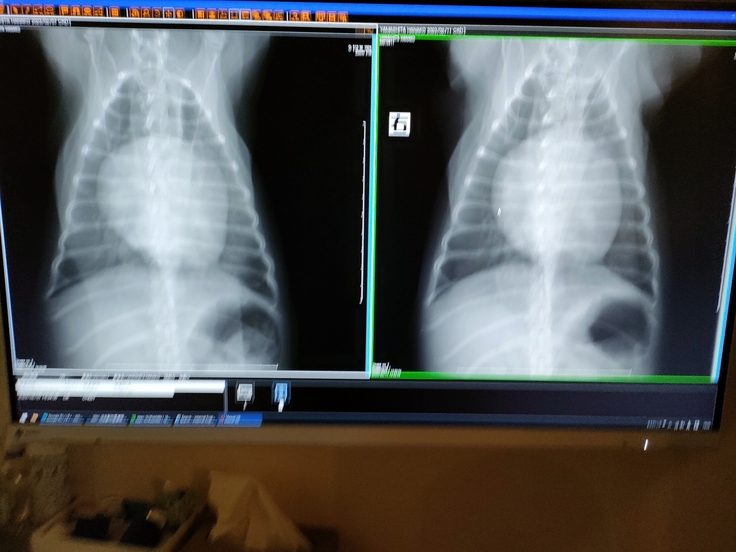

2023年1月頃に、急に呼吸促迫になり

慌てて病院に行きレントゲン結果から、

肺水腫になっていました。

僧帽弁閉鎖不全症ステージCになり、

いつ肺水腫が悪化するかわからない状態となりました。